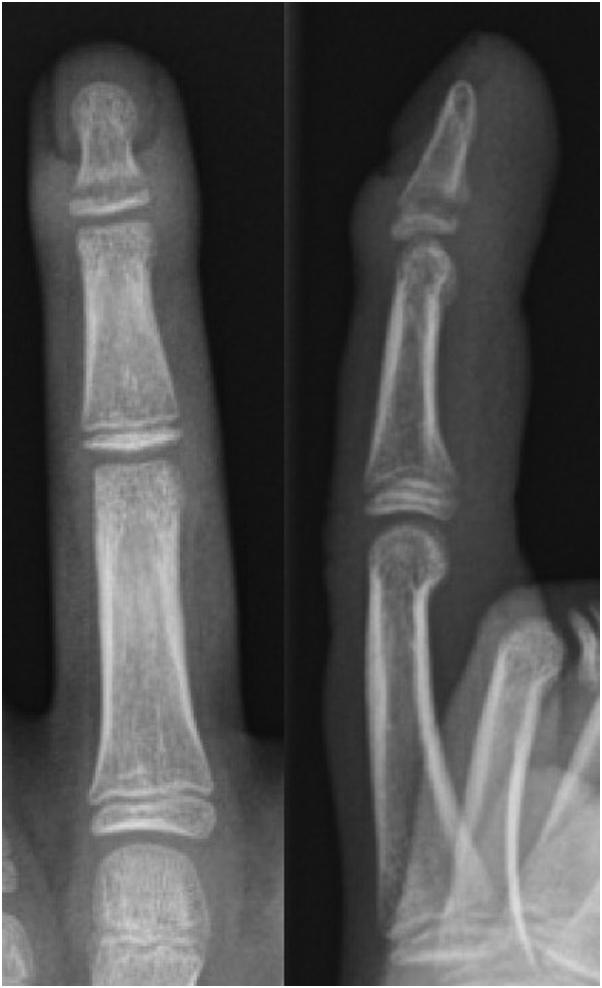

Seymour fractures are common injuries in the pediatric population. High rates of deep infection have been reported due to delayed presentation and subsequent treatment. This report describes the case of a 13-year-old male wrestler who presented 1 month after a finger injury that was later diagnosed as a subacute Seymour fracture with osteomyelitis. The patient underwent irrigation and debridement and fracture reduction stabilized with nonabsorbable suture fixation. After 6 weeks of intravenous antibiotics, the patient was recovering well, with radiographic evidence of fracture healing and clearance of infection. This case highlights the use of a single suture as a treatment option for fixation of unstable Seymour fractures with delayed presentation. The management of acute open distal phalangeal physeal fractures is well described in the literature; however, further investigations are warranted into the optimal management of chronically infected digits with unstable Seymour fractures.

西摩骨折是儿科人群中的常见损伤。据报道,由于就诊延迟和后续治疗,深部感染发生率很高。本报告描述了一名13岁男性摔跤运动员的病例,他在手指受伤1个月后就诊,后来被诊断为亚急性西摩骨折并伴有骨髓炎。患者接受了冲洗和清创,并采用不可吸收缝线固定稳定骨折复位。静脉注射抗生素6周后,患者恢复良好,有骨折愈合和感染清除的影像学证据。该病例强调了使用单根缝线作为延迟就诊的不稳定西摩骨折固定的一种治疗选择。文献中对急性开放性远端指骨骨骺骨折的处理有详细描述;然而,对于慢性感染且伴有不稳定西摩骨折的手指的最佳处理方法,仍需进一步研究。